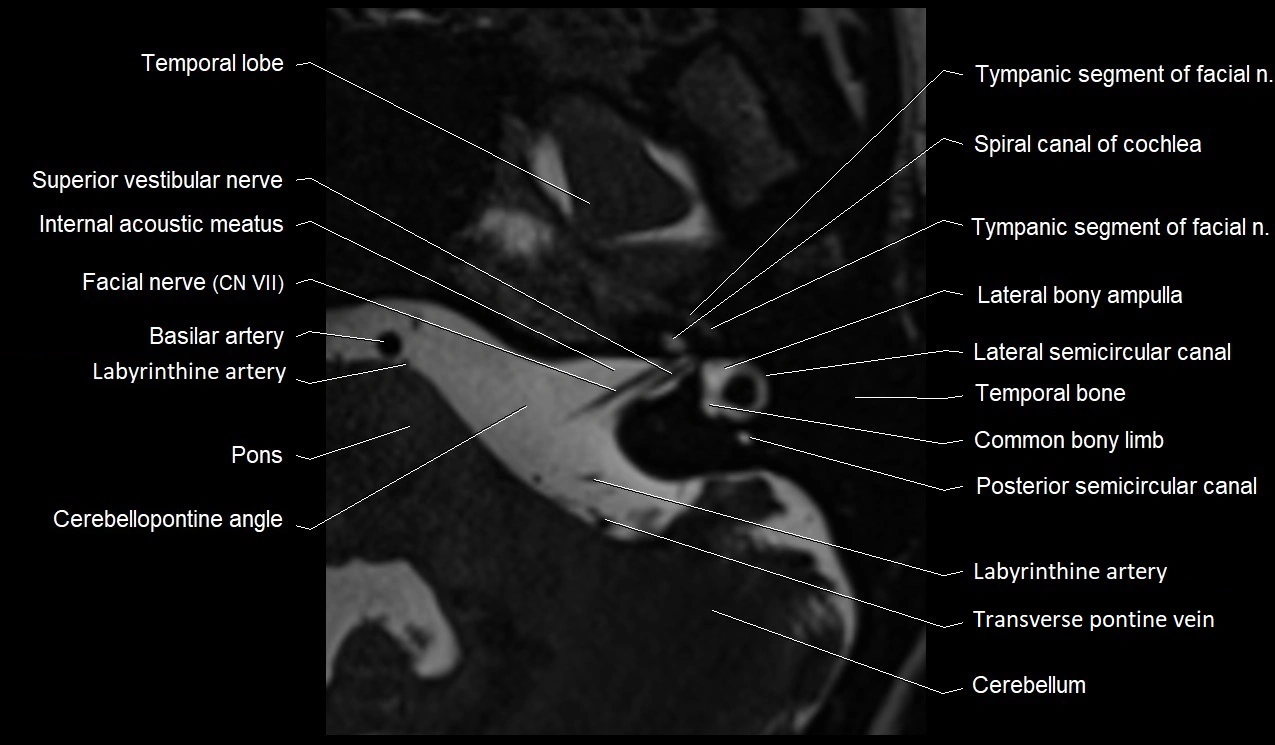

MRI images

image